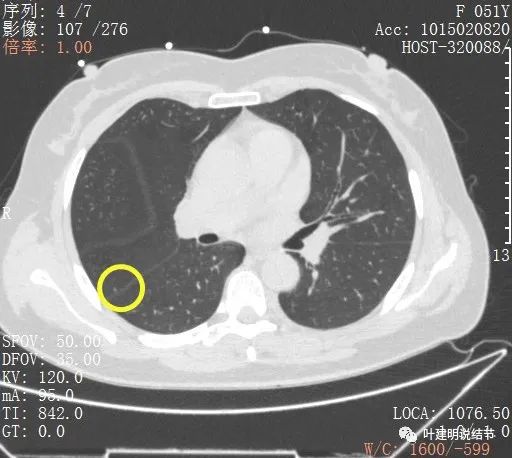

上圖示病灶A,當時很淡,三角形,邊緣模糊,其實更像區域性炎性病灶。

綜上所述,病軒A風險程度高,基本上應該是浸潤性腺癌,因為這麼小,是混合磨玻璃,且實性成分佔比較高,所以可能是至少腺泡型為主(也可能含更高風險亞型)伴貼壁成分(因為有磨玻璃成分,雖佔比少);B病灶考慮不典型增生可能性大,不能排除原位腺癌,若沒有A在,它可安全隨訪;C病灶考慮至少原位腺癌,也可能是微浸潤性腺癌,因為密度較高。若病為A在,它也因為過小,可隨訪。好在三個病灶都在上葉後段,那麼如果做上葉後段切除能一次解決目前所有病灶。所以我是建議其儘早手術的。今天要分享這個病例的目的還不是在這,而是我們再來看她2年前的片子,看病灶情況的演變,帶給我們的思考。先看其2年前的片子: